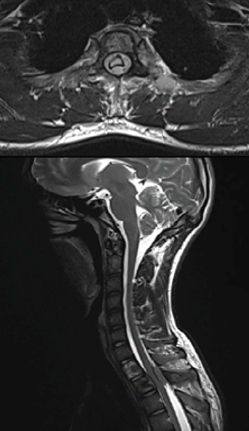

Spinal Aneurysmal Bone Cyst in a Pregnant Patient Presenting with Neurological Symptoms: A Case Report

Bishal Guin , Deepthy Balakrishnan , Arunkumar Sekar , Pavithra Ayyanar

………………………………p.30-33